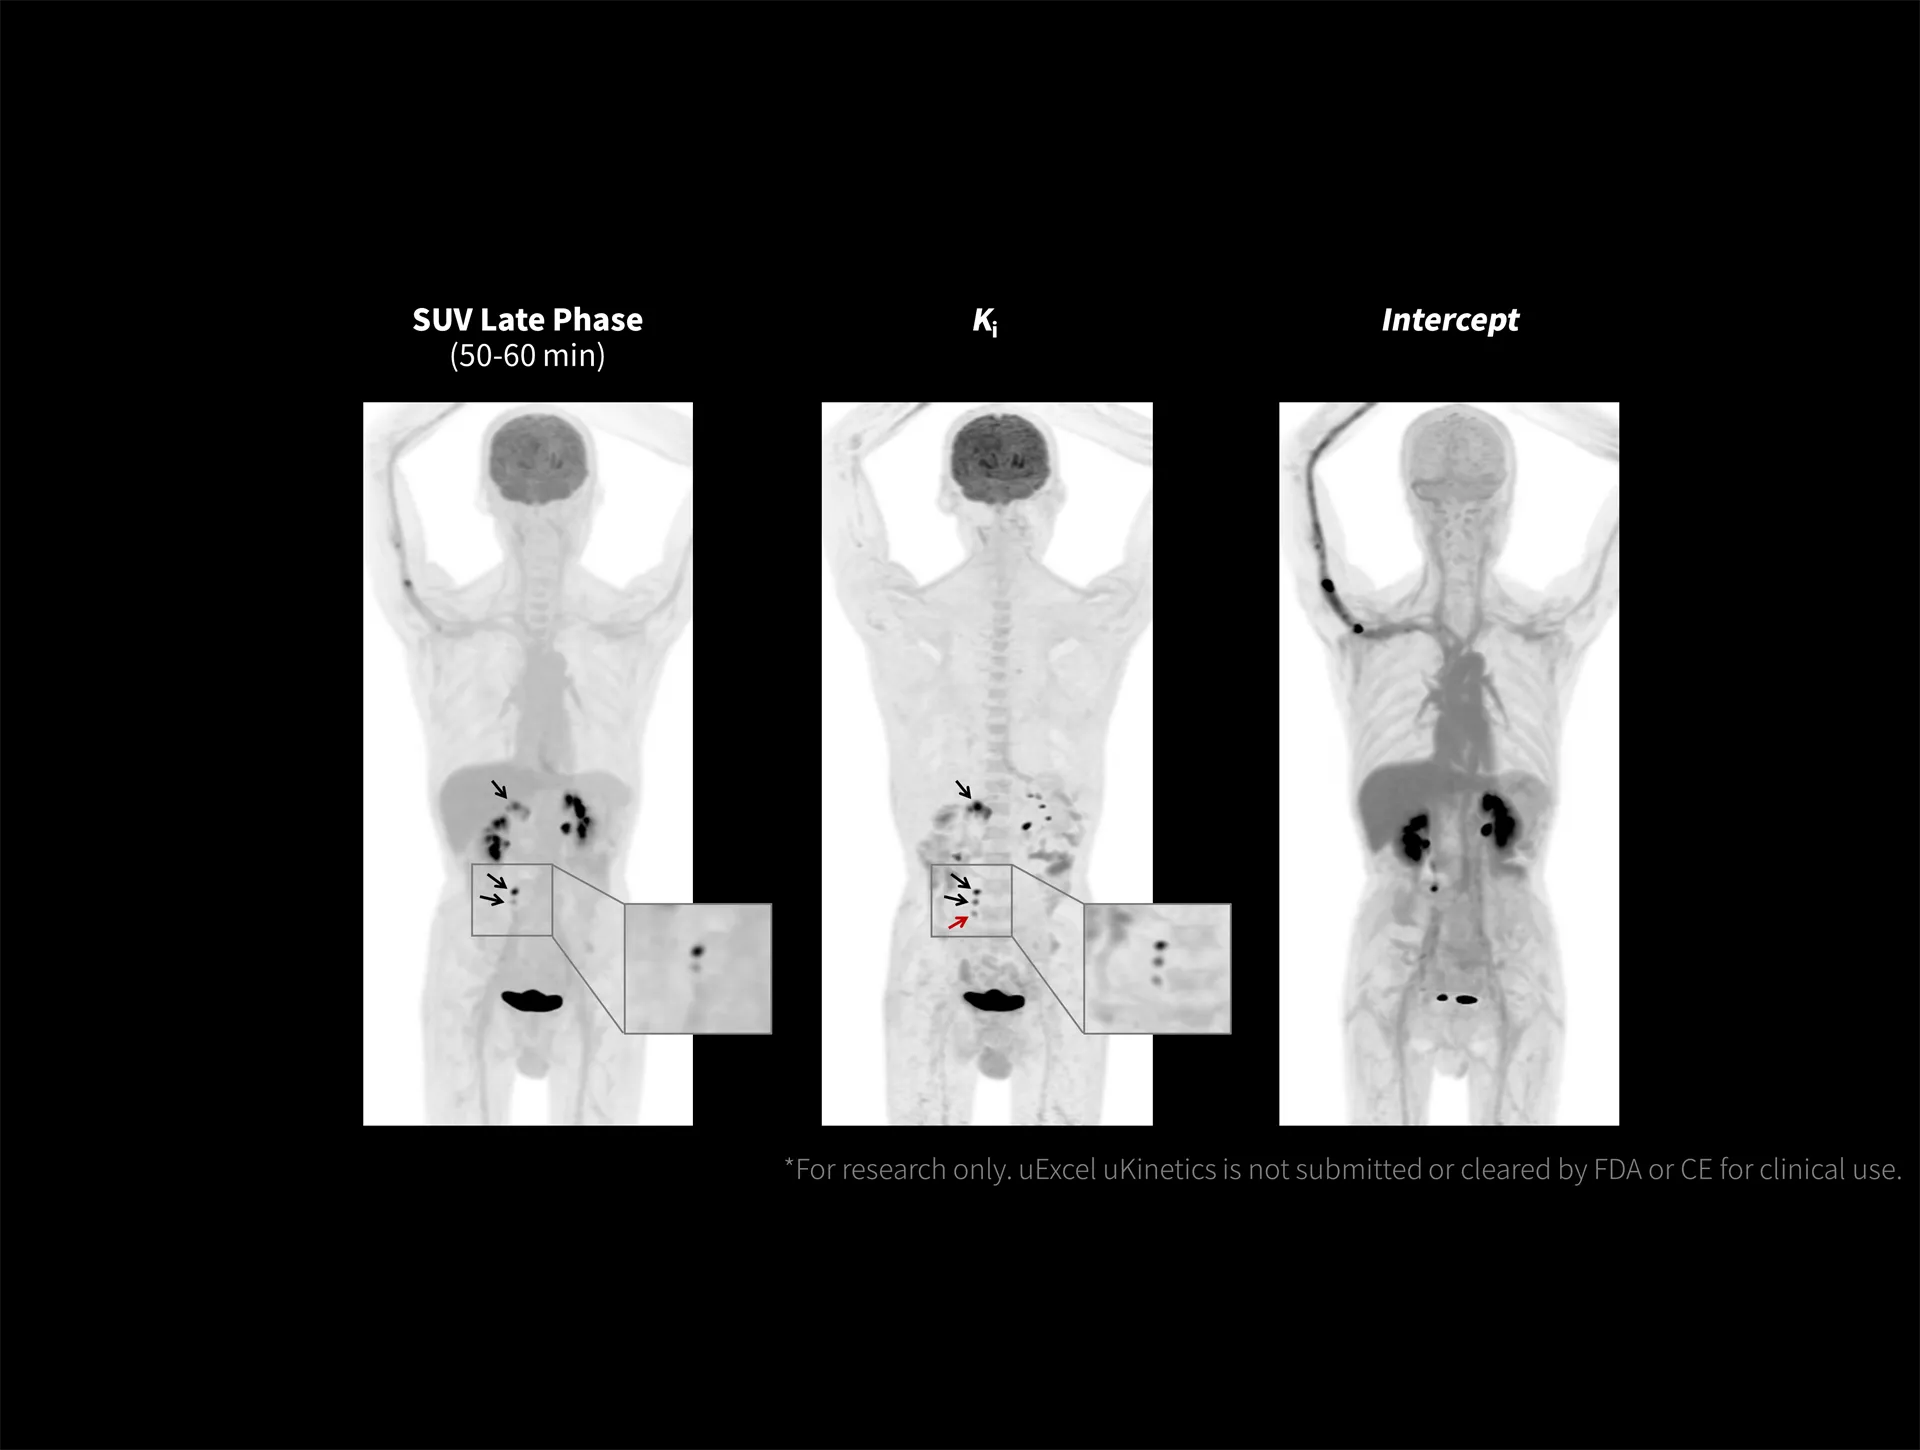

With the ultra-high system performance, uMI Panorama faces up to the challenges of tracers with different half lives and the complex scanning conditions, without compromise for image quality.

Venture beyond traditional boundaries and embrace a future of breakthroughs with uMI Panorama. It delivers consistently high performance across different tracers or concentrations, supporting versatile clinical or research applications to meet your needs today and tomorrow.